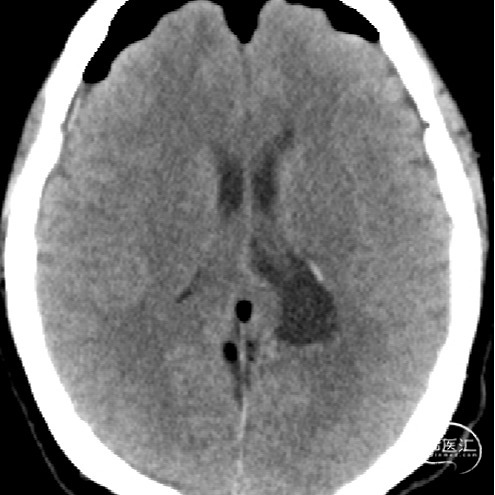

外院影像考虑脑膜瘤?室管膜瘤?

诊断:1.颅内占位性病变(左侧侧脑室三角区,脑膜瘤)2.高血压

术前情况

2023.04.21外院MR

1.结合病史体征及辅助检查诊断左侧侧脑室三角区脑膜瘤明确;

2.肿瘤具有明显的占位效应,无明显的手术禁忌,故手术切除指征明确;